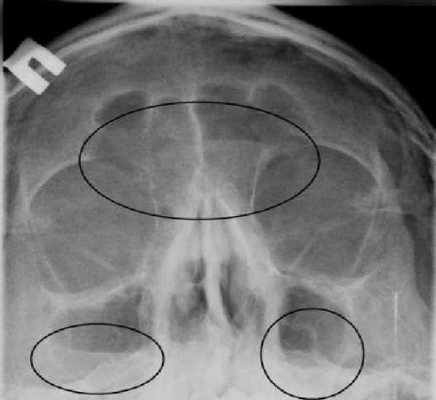

УКЛАДКИ СНИМОК ГЛАЗНИЦЫ В НОСОПОДБОРОДОЧНОЙ ПРОЕКЦИИ

Назначение снимка. Изучение состояния костей, образующих вход в глазницу, костной структуры верхней и наружной ее стенок.

Укладка больного для выполнения снимка сходна с укладкой для выполнения обзорного снимка в этой же проекции. В данном случае используюткассету размером 13X18 см, располагая ее в кассетодержателе в поперечном положении. Больной прилежит к столу подбородком и кончиком носа,переносье соответствует центру кассеты. Центральный пучок излучениянаправляют на центр кассеты. Фокусное расстояние—100 см.

В этой же укладке может быть выполнен снимок одной (правой или левой) глазницы. В таких случаях центр снимаемой глазницы соответствует центру кассеты, и на него отвесно направляют пучок излучения, используя тубус или диафрагмирование пучка излучения с помощью щелевой диафрагмы. Фокусное расстояние—100 см (рис. 88).

Информативность снимка. На снимке хорошо видны вход в глазницу, структура ее стенок, иногда малое и большое крыло клиновидной кости (рис. 89). На снимке в этой проекции могут быть выявлены деструктивные изменения стенок глазницы и инородные тела в ее полости (рис. 90, 91). Для выявления изменений в области верхней стенки глазницы (например, при

диагностике переломов) снимок целесообразно выполнять не в носоподбородочной, а в подбородочной проекции.

На таких снимках верхняя стенка глазницы проекционно искажается в меньшей степени, и все изменения в ее области видны более отчетливо (см. рис. 54, 55).

На прицельном снимке каждой из глазниц в этой же проекции, как правило, небольшие изменения структуры стенок, а также мелкие инородные тела глаза видны лучше. Такие снимки широко используют в офтальмологической практике (рис. 92).

Критерии правильности технических условий съемки и правильности укладки основываются на четкости выявления костной структуры и симметричности изображения глазниц.

Наиболее частые ошибки при выполнении снимка сводятся к асимметрии положения головы.